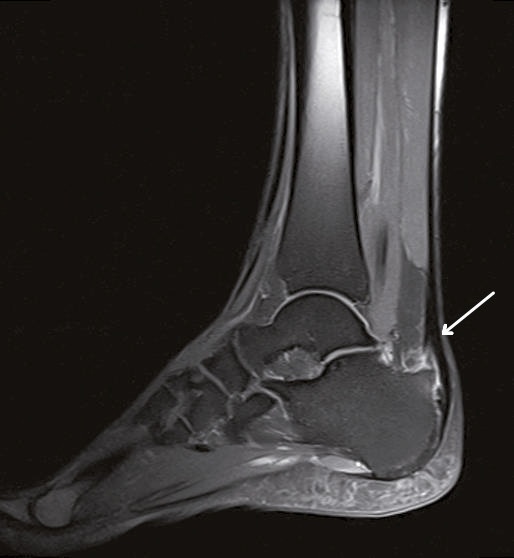

Die Persistenz der Beschwerden machte eine Vorstellung beim Facharzt für Orthopädie notwendig, der sonographisch eine Bursitis calcarea sowie eine Tendinitis der Achillessehne bei prominenter Haglundexostose diagnostizierte. Das in der weiteren Diagnostik durchgeführte Kernspintomogramm (MRT) zeigte zusätzlich eine Signalanhebung der präachillären Weichteile sowie ein zentrales Knochenmarködem im distalen Ansatzbereich des Kalkaneus.

bestehende Schmerzhaftigkeit der rechten Ferse, hier vor allem im Bereich 2 – 3 cm proximal des Ansatzes der Achillessehne am Kalkaneus. Eine erneute Bildgebung zur Kontrolle des Therapieerfolges mittels MRT zeigte hier weiterhin das Bild einer Tendinopathie bei Haglund-Exostose. Deshalb erfolgte eine intensive Beratung des Patienten hinsichtlich einer Operation nach Abschluss der immunmodulierenden Therapie, wofür sich der Patient aufgrund des immer noch hohen Leidensdruckes entscheiden konnte.

Ein einfacher Test zur Abgrenzung von einer Ruptur der Sehne mit Hämatom, Schwellung und eventuellem Tasten einer Delle ist nach wie vor der Simmonds-Thompson-Test (Plantarflexion des Fußes durch Kompression der Wadenmuskulatur bei intakter Achillessehne). Wie in der Kasuistik beschrieben, erfolgt die weitere Diagnostik mittels Sonographie der Ferse zur Darstellung einer Verdickung, Hypervaskularisation oder Zunahme von echoarmen Arealen. Zudem sollte eine Röntgenuntersuchung durchgeführt werden, um eine mögliche Haglund-Exostose zu detektieren. Eine Kernspintomographie der betroffenen Ferse eignet sich sehr gut zur Darstellung sowohl von strukturellen Veränderungen der Achillessehne, als auch begleitender Entzündungszeichen (siehe Abbildung 3).